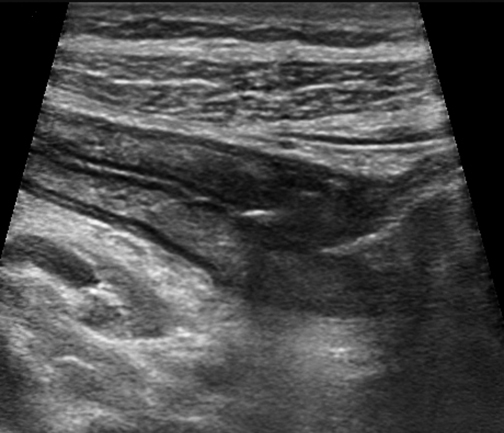

Cross sectional image of the terminal ileum show thickend boLongitudinal image of the terminal ileum show thickend bowel wall and

Cross sectional and longitudinal images of the terminal ileum show thickend bowel wall and inflammatory echogenic fat in a patient with acute CD of the terminal ileum.